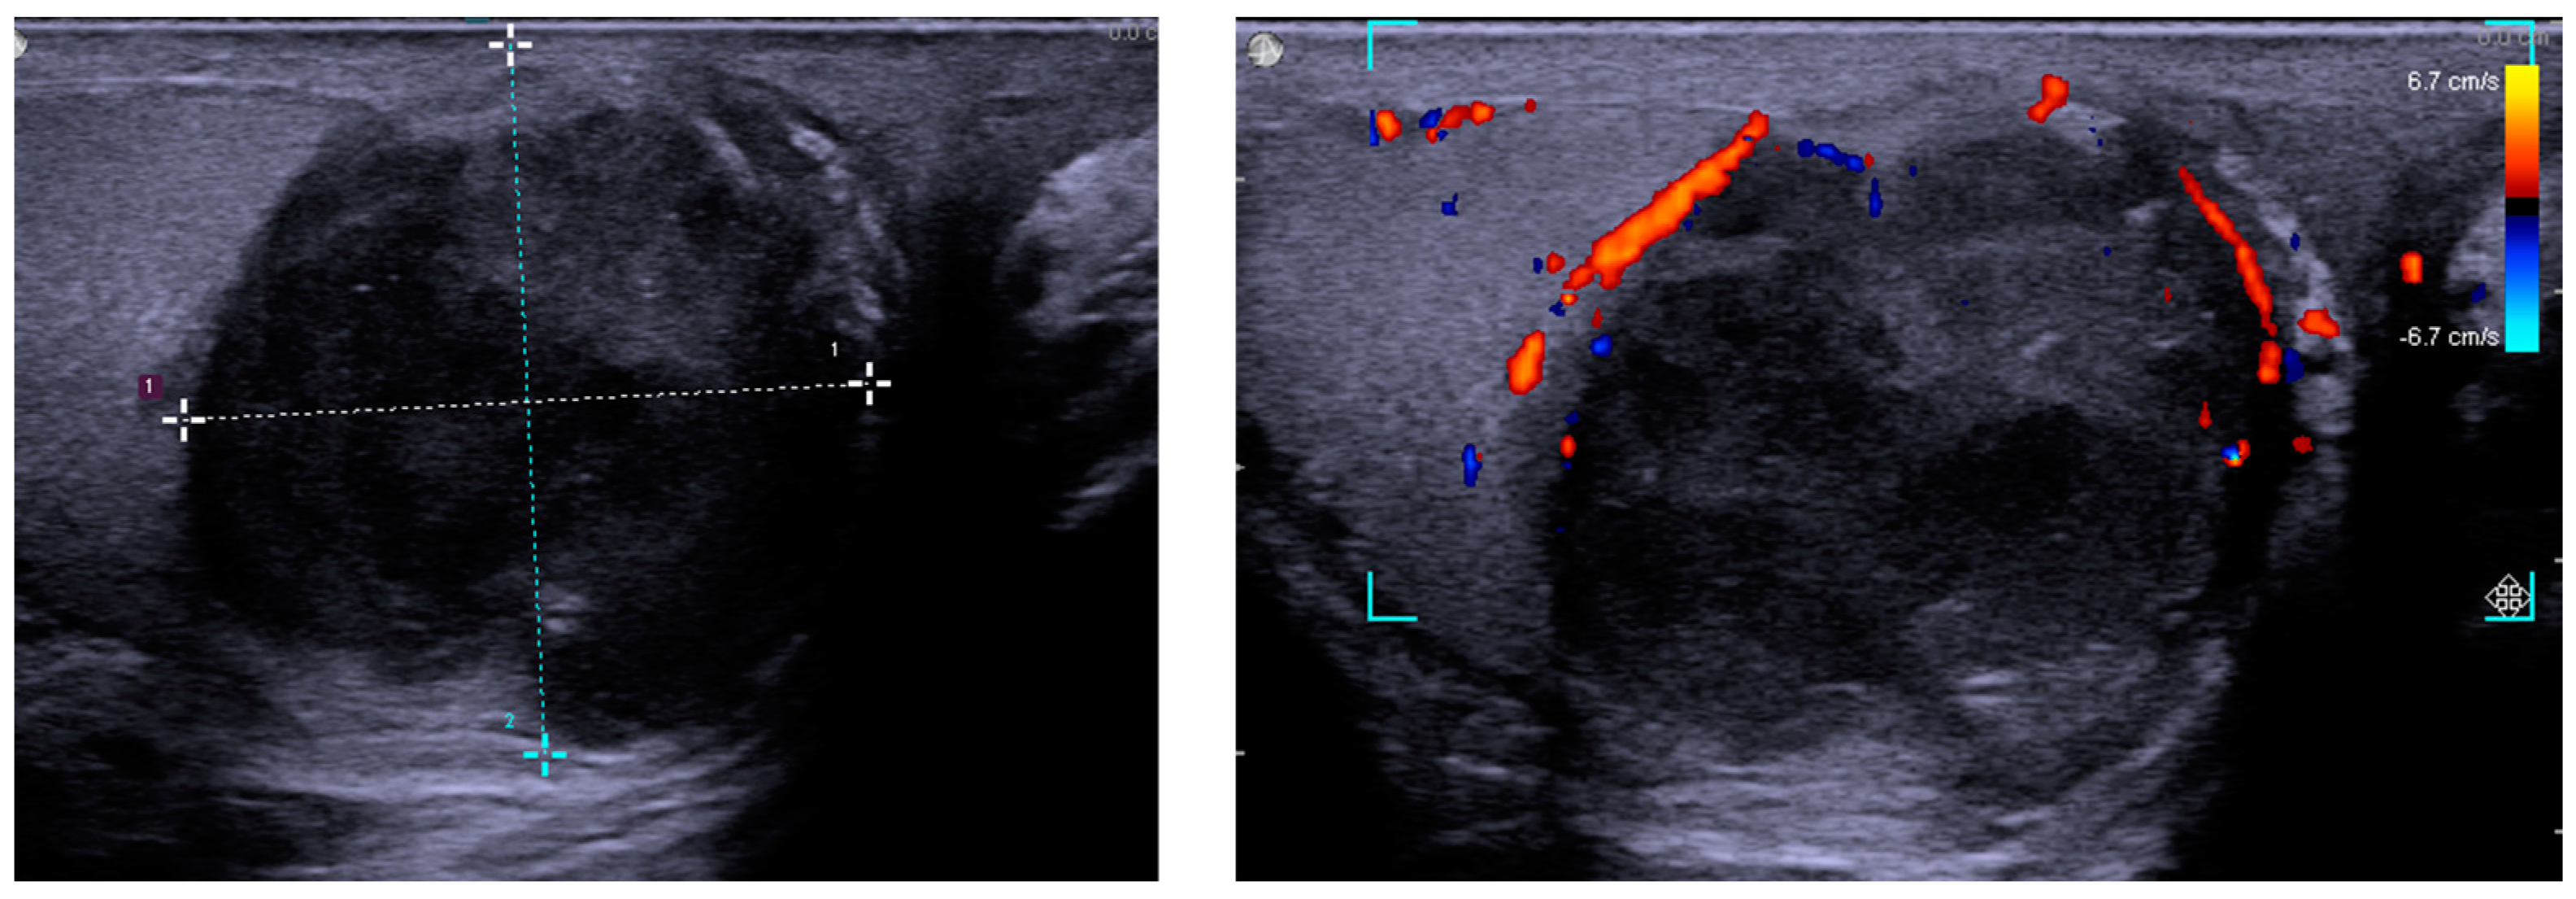

2. Case Presentation